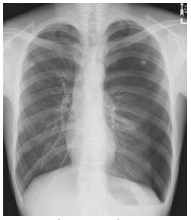

What chest projection is this?

PA Chest